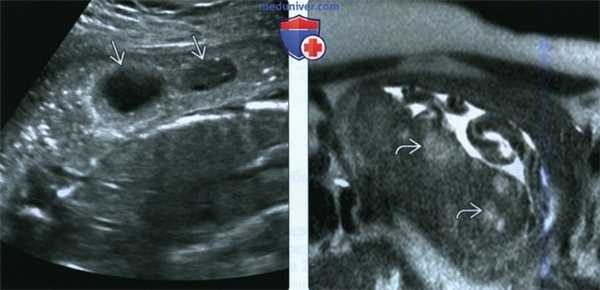

(Слева) ТВУЗИ по поводу placenta accreta. В плаценте визуализируются воронкообразные образования с кровотоком. Образования имеют более острые углы по сравнению с типичными РМВП. Также отмечается выбухание.

(Справа) Тот же случай. МРТ, Т2-ВИ. Сигнал, исходящий от кровотока в плацентарной лакуне, прерывается. Обращает внимание линейное строение образования. Лакуны нередко обнаруживают при неосложненной беременности, однако множественные крупные образования неправильной формы (как в данном случае) требуют более тщательного изучения.